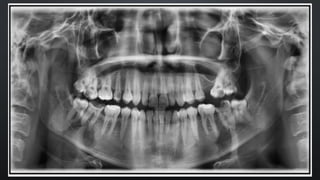

A radiografia panorâmica é uma técnica importante na odontologia que oferece uma

visão abrangente dos maxilares, dentes, articulações temporomandibulares (ATM) e

estruturas adjacentes. O método utiliza um feixe de raios X que se move em um arco

ao redor da cabeça do paciente, resultando em uma imagem bidimensional que

captura uma ampla área da arcada dentária.

Essa técnica é especialmente útil para:

•Avaliar a posição e o estado dos dentes, incluindo os dentes do siso.

•Diagnosticar problemas nas articulações da mandíbula.

•Identificar cistos, tumores e outras condições patológicas.

•Planejar tratamentos ortodônticos ou cirúrgicos.

A radiografia panorâmica é rápida, geralmente não requer preparação especial do

paciente e minimiza a exposição à radiação em comparação com radiografias

intraorais múltiplas. É uma ferramenta valiosa na prática clínica para o diagnóstico e

planejamento de tratamentos.